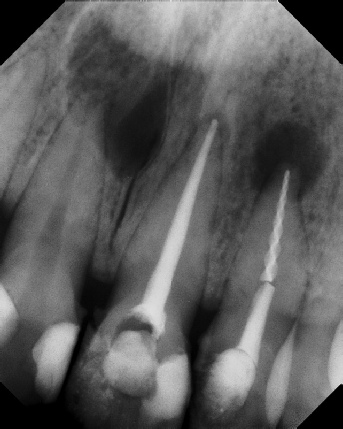

COMPLICATED ANATOMY LARGE LESIONS CALCIFIED CANALS PERFORATION / RESORPTION SEPARATED INSTRUMENTS SURGICAL CASES RETREATMENT / pOST REMOVAL OPEN APICES ACCESS THRU CROWNS Root Canal Case Portfolio

Pre-op Post-op 1 Post-op 2